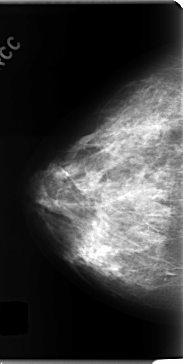

C_0150_1.RIGHT_CC

RIGHT_CC LINES 4720 PIXELS_PER_LINE 2368 BITS_PER_PIXEL 12 RESOLUTION 50 NON_OVERLAY